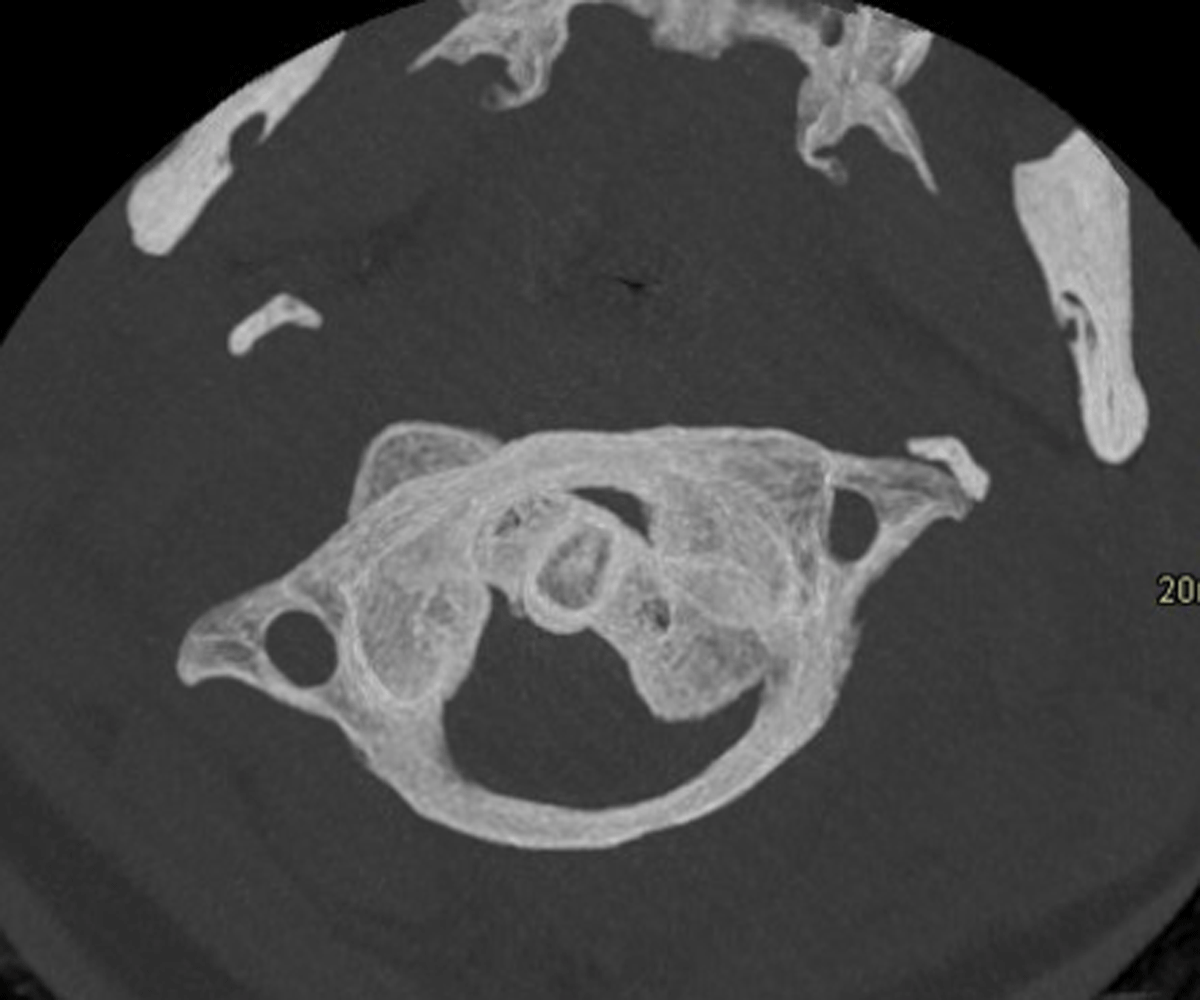

Figure 2

Atlas and axis rotate as one unit on CT with maximal contralateral head rotation.